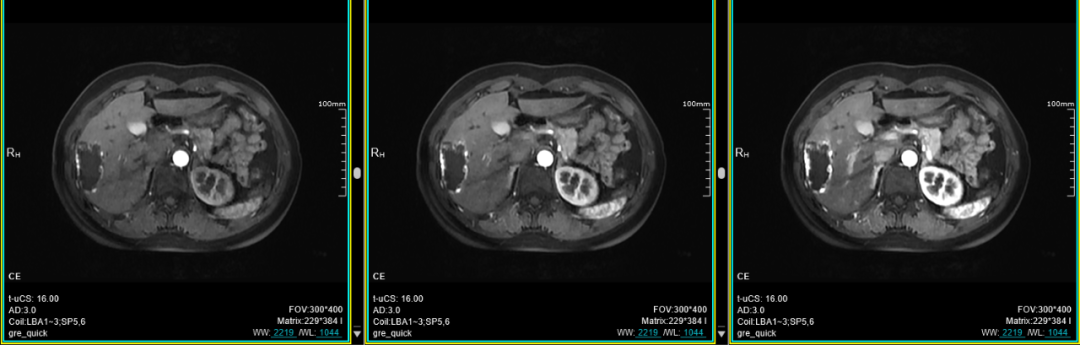

十、肝脏动脉期多期扫描技术(最多可达32期):此项检查技术主要应用于上腹部,尤其是应用于不同期相肝脏富血供肿瘤的检出上。

联影磁共振怎么样平原县第一人民医院联影uMR780 光梭3.0T磁共振正式投入使用,开启医学影像新时代!_https://www.jmylbn.com_新闻资讯_第27张

联影磁共振怎么样平原县第一人民医院联影uMR780 光梭3.0T磁共振正式投入使用,开启医学影像新时代!_https://www.jmylbn.com_新闻资讯_第28张